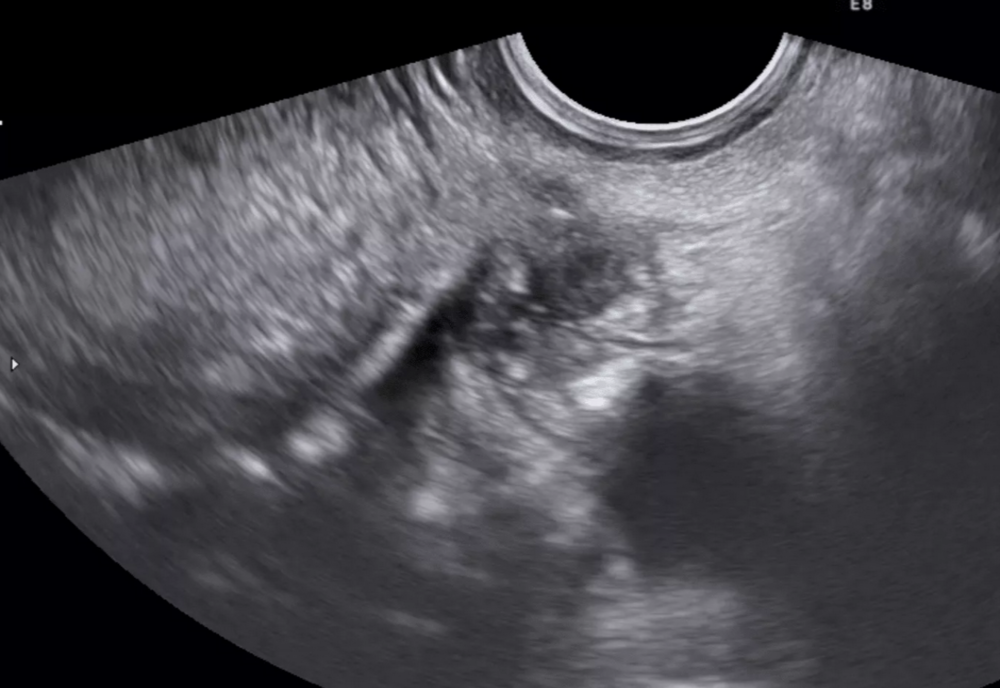

Endometrioza este o boală cronică ce afectează cel puțin una din nouă femei

Endometrioza este o boală cronică ce afectează cel puțin una din nouă femei și fete australiene. Simptomele includ dureri abdominale, menstruații abundente, balonare, sângerare de la vezică și intestin, oboseală, anxietate declanșată de durere și infertilitate.